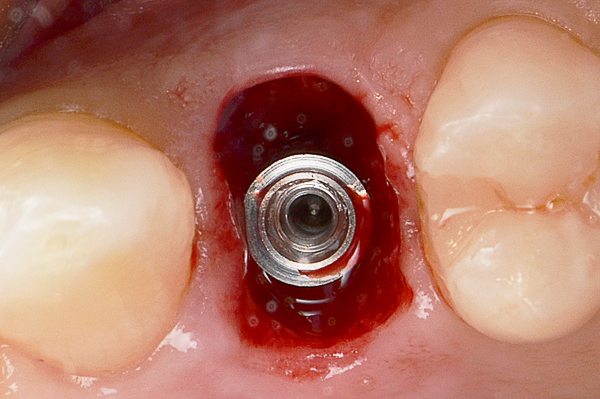

A seguito dell'analisi radiografica viene pianificata l'estrazione atraumatica del premolare con l'inserimento contestuale di un impianto Shelta. La riabilitazione immediata viene eseguita con un pilastro XA per protesi avvitata, su cui viene fissato un provvisorio realizzato in laboratorio secondo i principi dei profili di emergenza della tecnica B.O.P.T.

Donna, 37 anni, non fumatrice, con una buona igiene, si presenta in studio con un fallimento del trattamento endodontico dell'elemento 1.4.